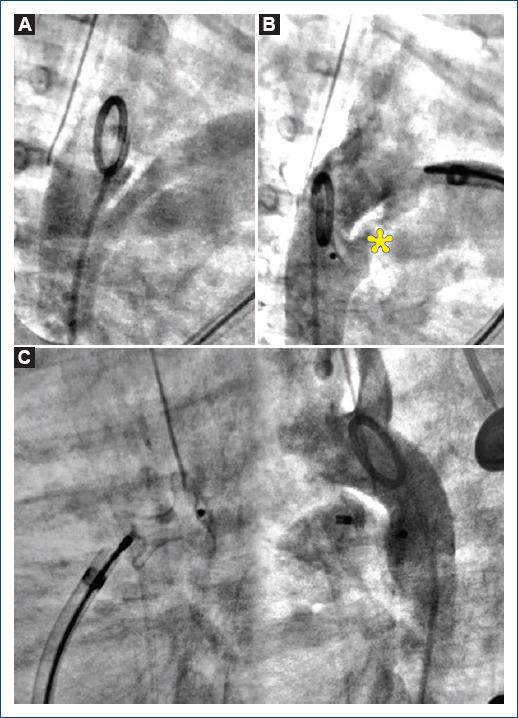

[Ductal spasm versus angiographic variations during patent ductus arteriosus transcatheter closure: case report].

{"title":"[Ductal spasm versus angiographic variations during patent ductus arteriosus transcatheter closure: case report].","authors":"Roberto Mijangos-Vázquez, Andrea Castillo-González","doi":"10.24875/ACM.24000104","DOIUrl":null,"url":null,"abstract":"","PeriodicalId":93885,"journal":{"name":"Archivos de cardiologia de Mexico","volume":" ","pages":"241-244"},"PeriodicalIF":0.0000,"publicationDate":"2025-02-19","publicationTypes":"Journal Article","fieldsOfStudy":null,"isOpenAccess":false,"openAccessPdf":"https://www.ncbi.nlm.nih.gov/pmc/articles/PMC12324848/pdf/","citationCount":"0","resultStr":null,"platform":"Semanticscholar","paperid":null,"PeriodicalName":"Archivos de cardiologia de Mexico","FirstCategoryId":"1085","ListUrlMain":"https://doi.org/10.24875/ACM.24000104","RegionNum":0,"RegionCategory":null,"ArticlePicture":[],"TitleCN":null,"AbstractTextCN":null,"PMCID":null,"EPubDate":"","PubModel":"","JCR":"","JCRName":"","Score":null,"Total":0}